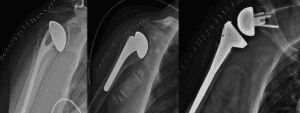

- Surgical Management:

- Needed for displaced or unstable fractures.

- ORIF (Open Reduction and Internal Fixation): Aligning and fixing the bones with plates and screws.

- Intramedullary Nailing (IM):Inserting a rod into the bone to stabilize the fracture.

Arthroplasty: Joint replacement surgery for severe fractures